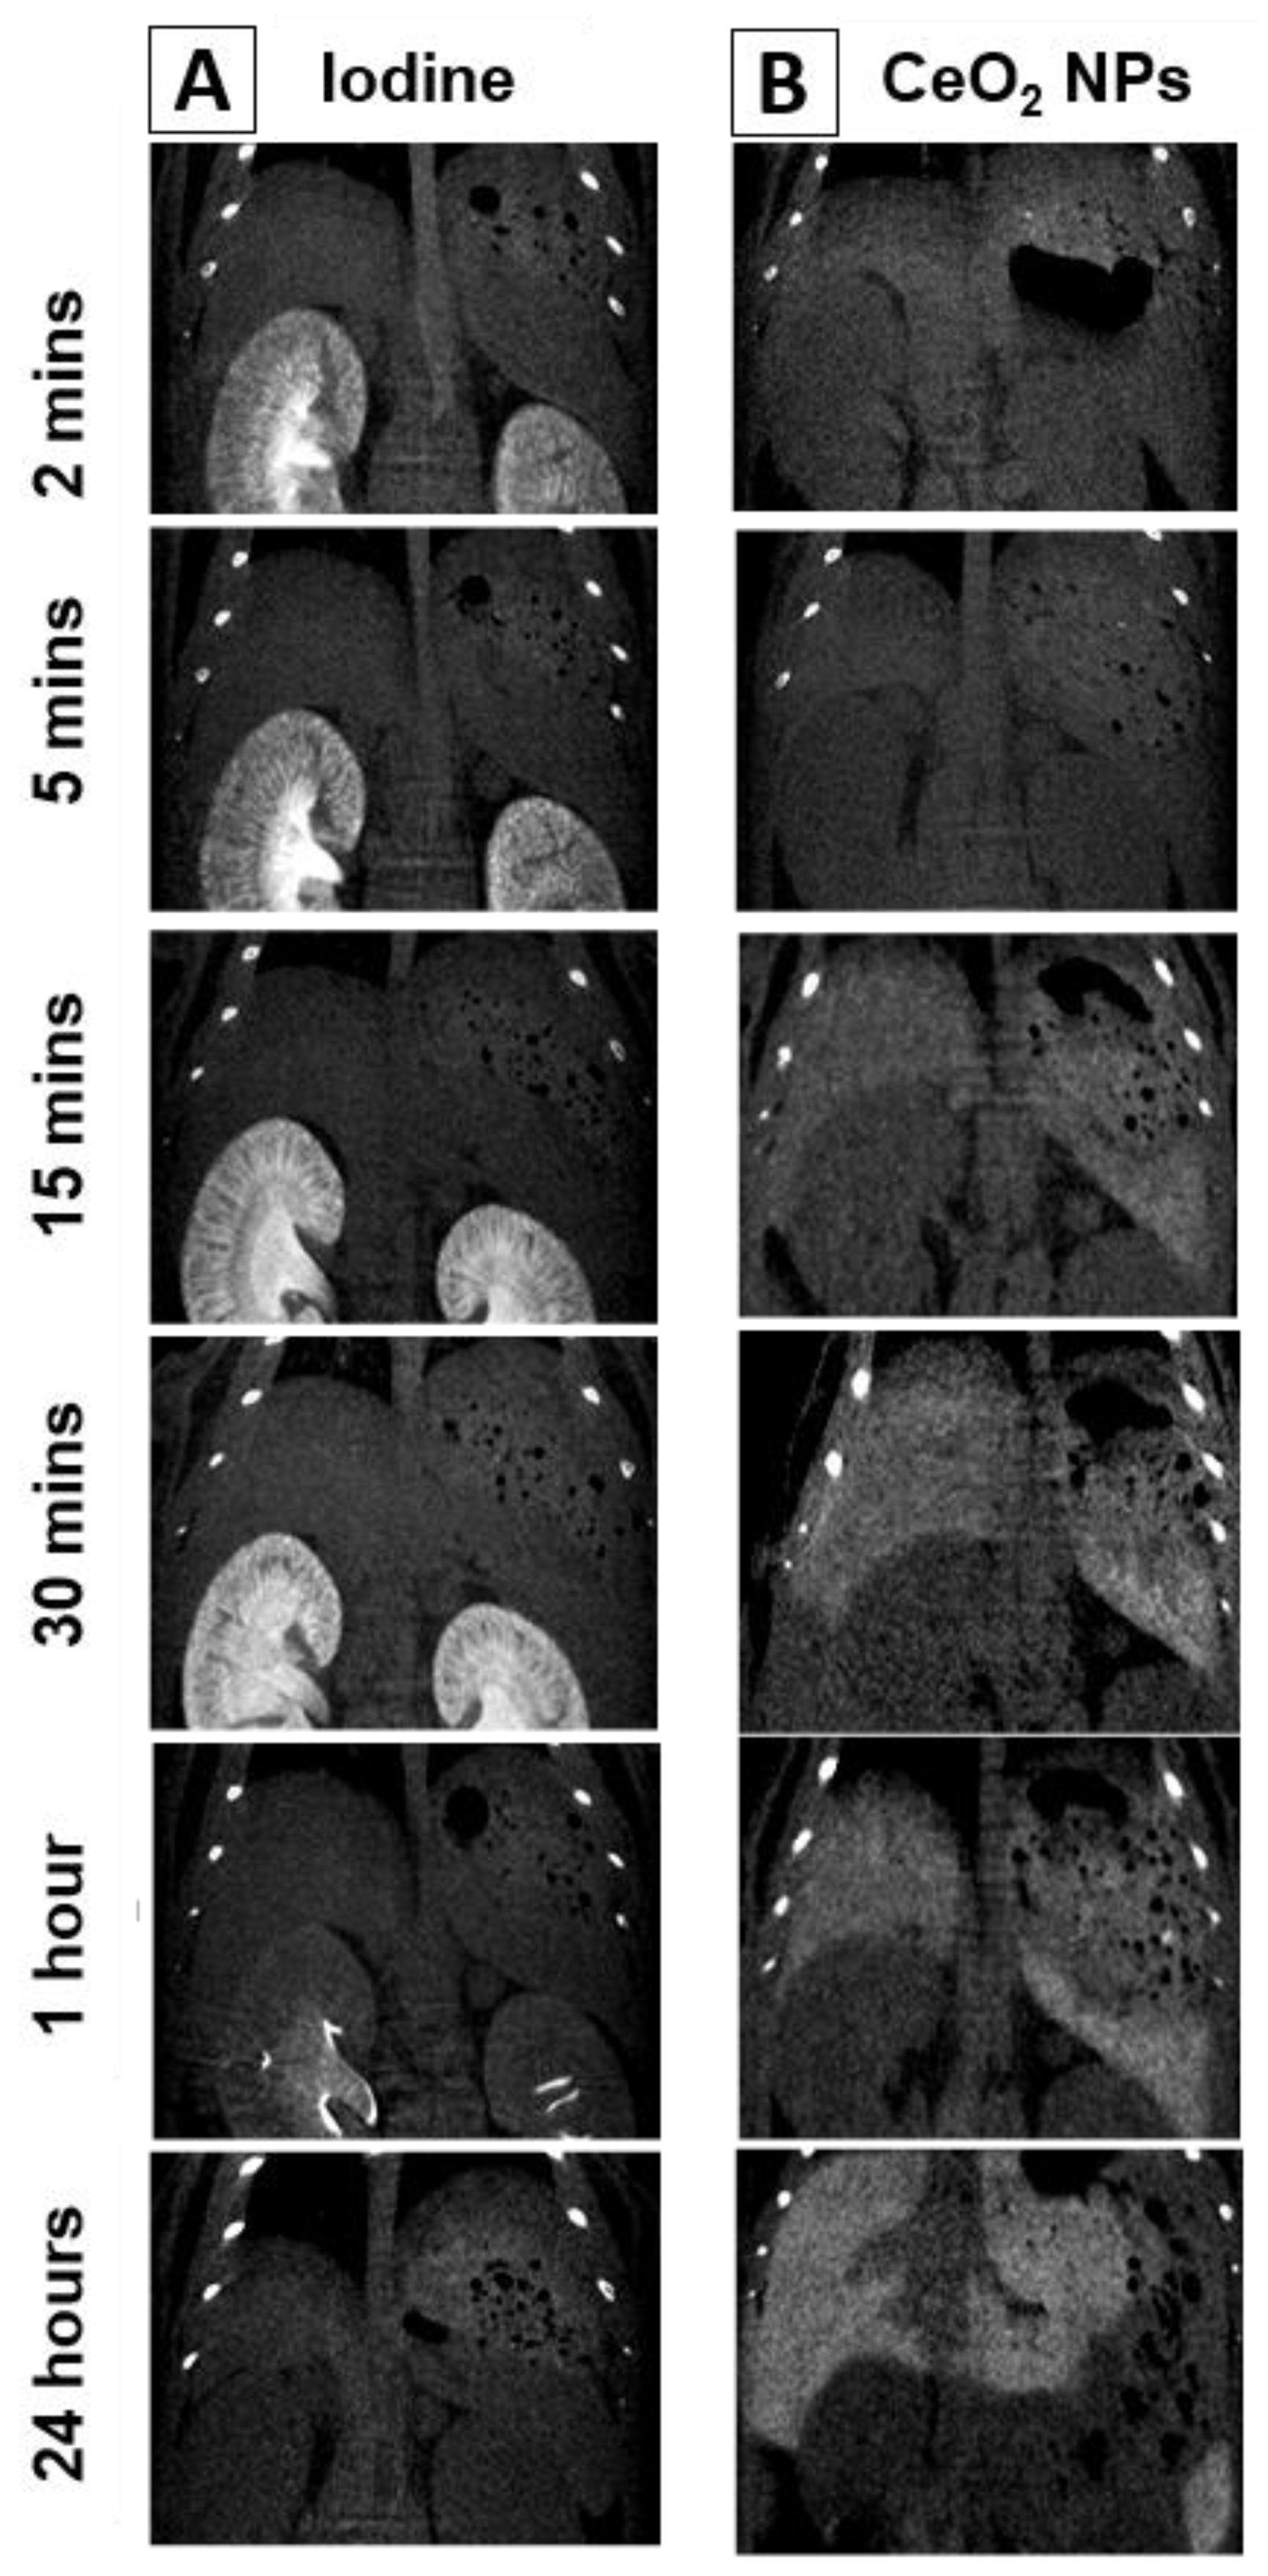

1. Introduction

2. Results and Discussion